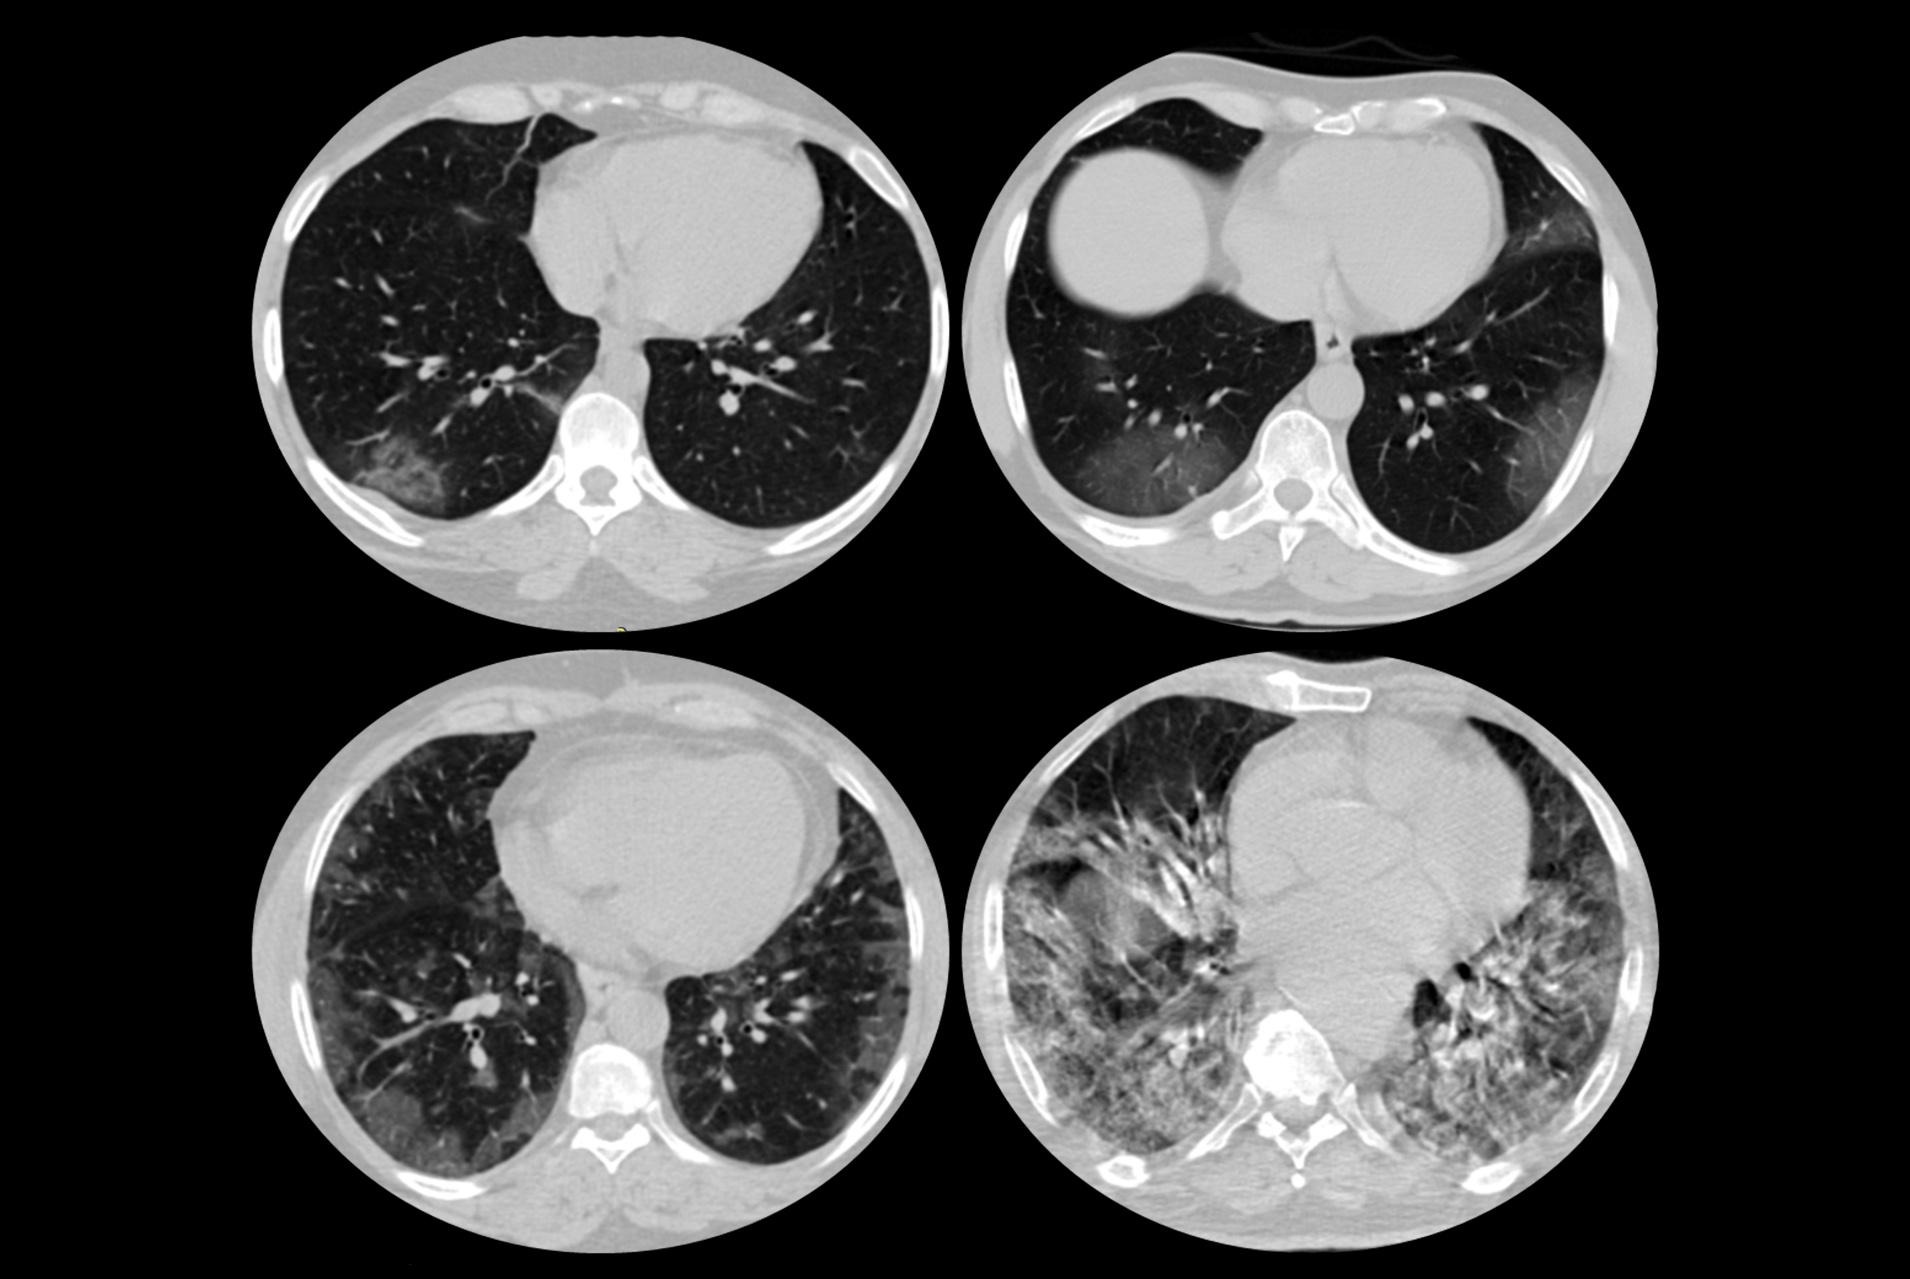

Chest computer tomography (CT) is being used extensively in patients with known and suspected COVID-19 infection, especially when there is limited availability of conventional testing with nasal or oral swab (PCR). Some patients may need to undergo multiple chest CT scans as part of their medical examination.